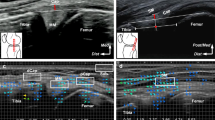

The joint capsule was confirmed to be not histologically independent of the medial meniscus over the entire circumference (Fig. 4a–f). The joint capsule was attached to the posteromedial tibia via fibrocartilage, even where the width of the capsular attachment was narrow (Fig. 4d,e). In addition, the upper margin of the capsular attachment reached the lower margin of the articular cartilage without a gap in any histological section. The semimembranosus was in close contact with the posterior joint capsule (Fig. 4b) and was gradually covered by a loose tendinous sheath at the posteromedial region (Fig. 4c). Furthermore, it was completely covered by a dense fibrous sheath, which was continuous with the posteromedial joint capsule from the posterior to the anterior edge of the proximal tibial attachment (Fig. 4d,e). At the medial side of the tibia anterior to the semimembranosus attachment, the dense fibrous membrane, which was also continuous with the joint capsule, occupied the same layer as the dense fibrous sheath of the semimembranosus (Fig. 4f). The above-mentioned histological findings were based on sagittal and coronal sections of different specimens; however, the radial sequential images obtained from the micro-CT analysis confirmed the layered characteristics from the posterior to medial knee in the same specimen (Fig. 5 and Supplementary Video S1).

Histological analysis of the joint capsule and semimembranosus (Masson’s trichrome staining). Schematic illustration (a), the posteromedial aspect of the right medial knee, indicates histological section locations in sagittal (b and c) and coronal sections (d–f). The joint capsule (Cap) is not histologically independent from the medial meniscus (MM) and attaches to the superior edge of the tibia without any distance from the articular cartilage. The semimembranosus (Sm) is in close contact with the posterior Cap (b); it is gradually covered by a loose tendinous sheath at the posteromedial region (c) and completely covered by a dense fibrous sheath continuous with the Cap at the proximal tibial attachment (Star, d, e). Scale bars = 2.5 mm. Gcm Medial head of the gastrocnemius, Gr Gracilis, MIT Medial intercondylar tubercle, PCL Posterior cruciate ligament, Po Popliteus, Sa Sartorius, St Semitendinosus, Triangle Posterior root area of the MM, Inf Inferior, Med Medial, Lat Lateral, Post Posterior, Sup Superior.

Serial radial sections of the joint capsule and semimembranosus using phosphotungstic acid-enhanced micro-CT. Horizontal enhanced micro-CT image using phosphotungstic acid (a) indicates the radial slice locations centered around the medial intercondylar tubercle (MIT) for visualizing the following sections: images with 15° (b), 30° (c), 45° (d), 75° (e), 90° (f) clockwise from sagittal sections. Scale bars = 5 mm. Cap Joint capsule, Gcm Medial head of the gastrocnemius, Gr Gracilis, MM Medial meniscus, Po Popliteus, Sa Sartorius, Sm Semimembranosus, St Semitendinosus, Star Sm attachment on the superior edge of the tibia, Ant Anterior, Lat Lateral.